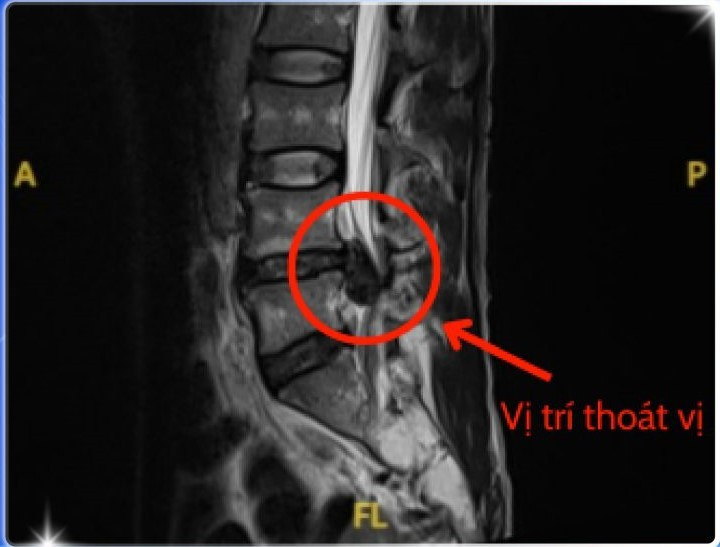

Sau khi thăm khám kỹ lưỡng và thực hiện chụp cộng hưởng từ (MRI) vùng cột sống thắt lưng. BS.CKI. Nguyễn Thế Thuần, Trưởng khoa Ngoại Thần Kinh chẩn đoán anh bị thoát vị đĩa đệm L4, L5 gây chèn ép thần kinh nặng.

Hình ảnh MRI cho thấy vị trí thoát vị - Ảnh BVCC